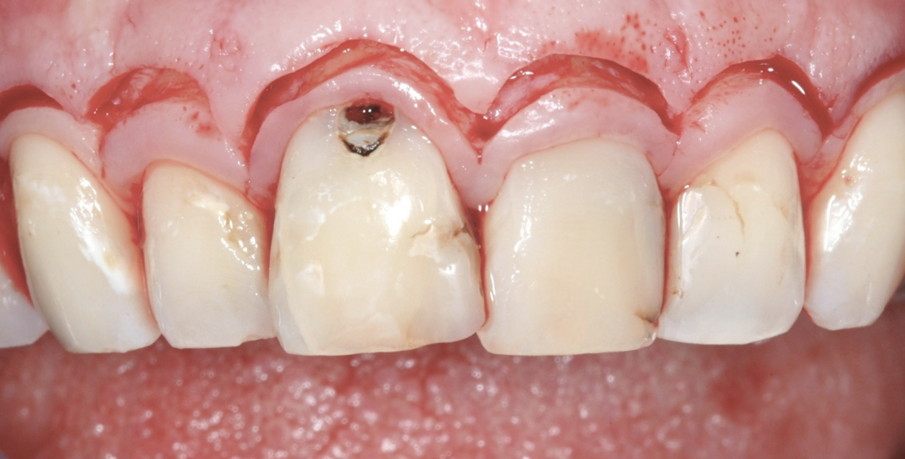

Una giovane paziente di 31 anni, si presenta al mio studio per risolvere l’inestetismo provocato dalla presenza di carie al colletto dell’11, e asimmerie delle parabole. Gli elementi frontali dal 12 al 22 presentavano inoltre diverse carie della corona clinica e contestualmente delle radici trattate in modo incongruo, tanto da provocare delle lesioni endodontiche molto ampie.

Figg. 1, 2 - Situazione iniziale.